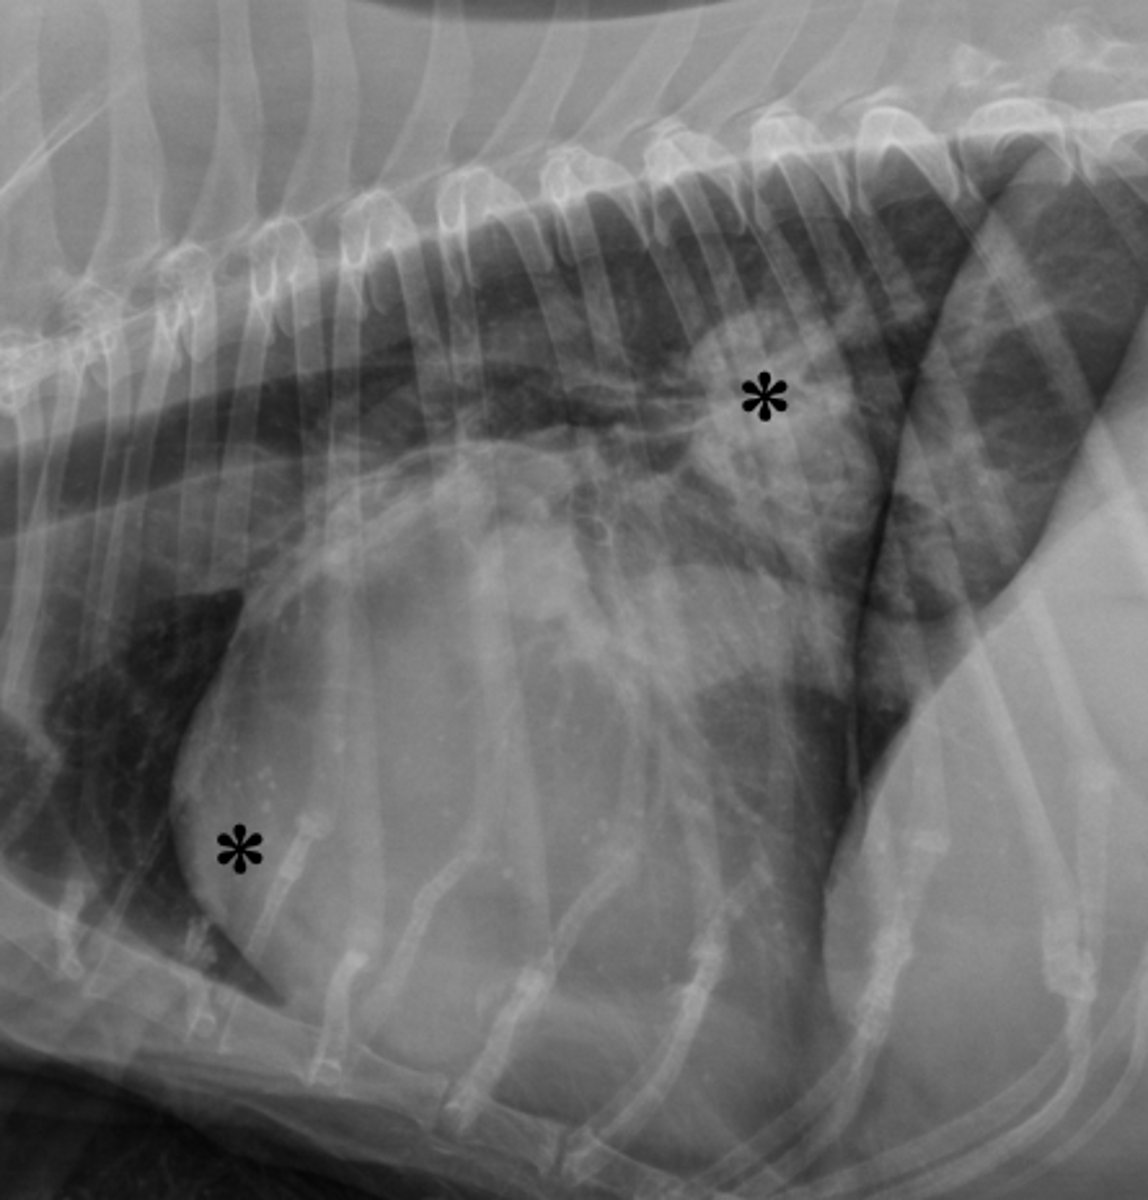

4. LA and RV

In the radiographic image of a dog seen below. What cardiac chambers as indicated by an asterisks (*) are enlarged?

1. LA and LV

2. LA and pulmonary artery

3. RA and RV

5. LV and RV